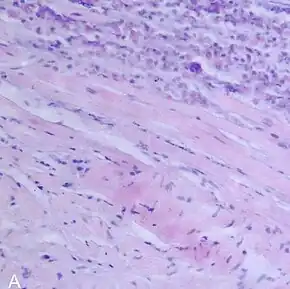

Endomyocardial biopsy showing myocarditis | |

EMB has a role in the diagnosis of viral myocarditis and inflammatory myocarditis.[1]